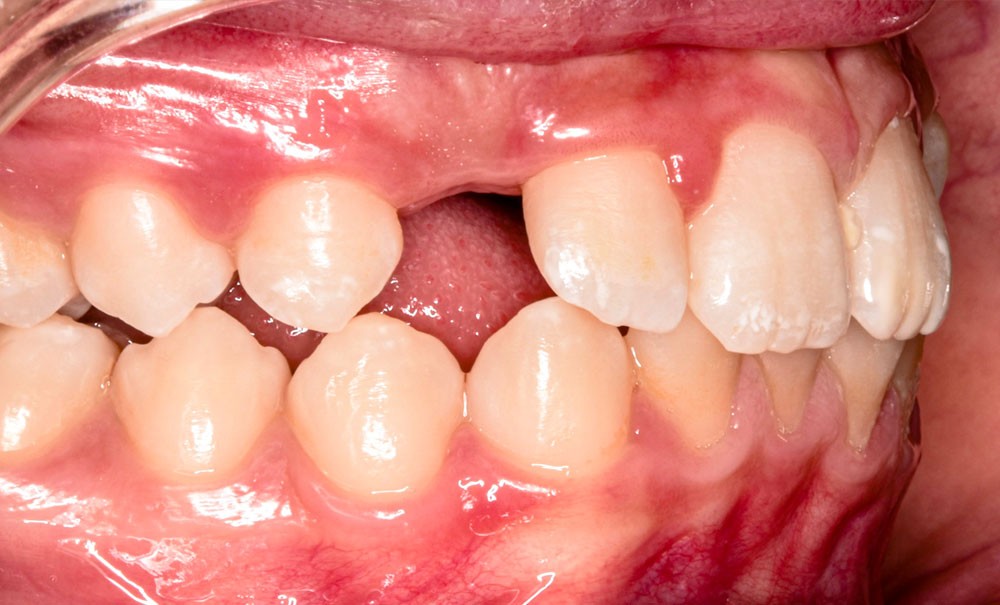

- Classe II subdivision gauche avec déviation du point inter-incisif mandibulaire à gauche ;

- occlusion inversée entre 22 et 32 ;

Le moment de l’extraction est essentiel : à cet âge, les deuxièmes molaires n’ont pas terminé leur édification radiculaire, ce qui favorise leur mésialisation [2]. Néanmoins, la direction d’éruption, surtout mandibulaire, reste difficile à prévoir, et la présence des troisièmes molaires ne garantit pas leur éruption correcte [3].

Le choix d’extraction dépend de l’âge, du stade de développement des secondes molaires, de la présence des troisièmes molaires, de la DDA et des relations squelettiques.

Des élastiques intermaxillaires de Classe II (1/4’’, 4 oz) ont renforcé l’ancrage et corrigé la relation sagittale. La mésialisation de 37 et 47 s’est faite progressivement, avec contrôle des axes et de l’inclinaison radiculaire.